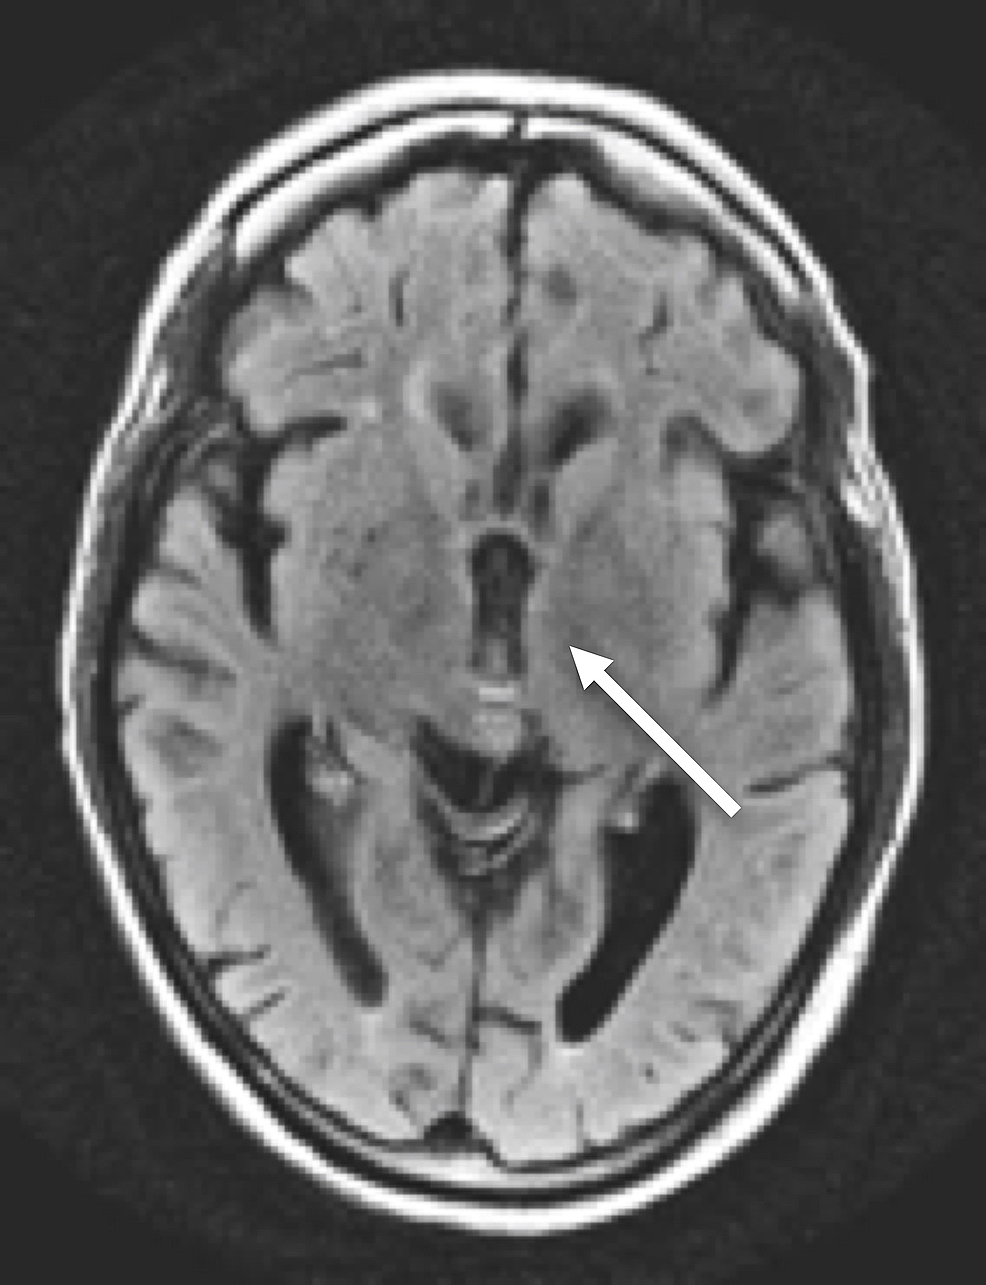

A CT of her brain revealed cerebellar vermian atrophy but was otherwise unremarkable (Figure 1).

MRI of her brain demonstrated cerebellar volume loss, increased FLAIR signal in the cerebellar vermis, normal corpus callosum and normal mammillary bodies (Figures 2-7).

Although not required for a diagnosis of acute WE, “typical” MRI findings include hyperintense FLAIR/T2 signal in the thalami, mammillary bodies, tectal plate, periphery of the third ventricle, and periaqueductal area [3,6]. Approximately 50% of patients with WE exhibit “atypical" MRI findings including FLAIR/T2 hyperintensity in the superior cerebellum, cranial nerve nuclei, red nuclei, dentate nuclei, caudate nuclei, splenium, and cerebral cortex [6]. Historically, these “typical” findings were thought to be more associated with alcoholics while the “atypical” findings were more associated with non-alcoholics. However, recent literature suggests that “typical” and “atypical” findings are less closely linked to alcohol-related and non-alcohol related WE than previously reported, as in our patient with alcohol-related WE displaying only “atypical” MRI features [7]. Differential diagnosis in patients with MRI findings of WE would include arterial/venous infarction (expected to show restricted diffusion), viral encephalitis (expected to have greater areas of increased FLAIR/T2 signal; atrophy would be unusual) and Marchiafava-Bignami Disease (expected to have callosal signal abnormality).